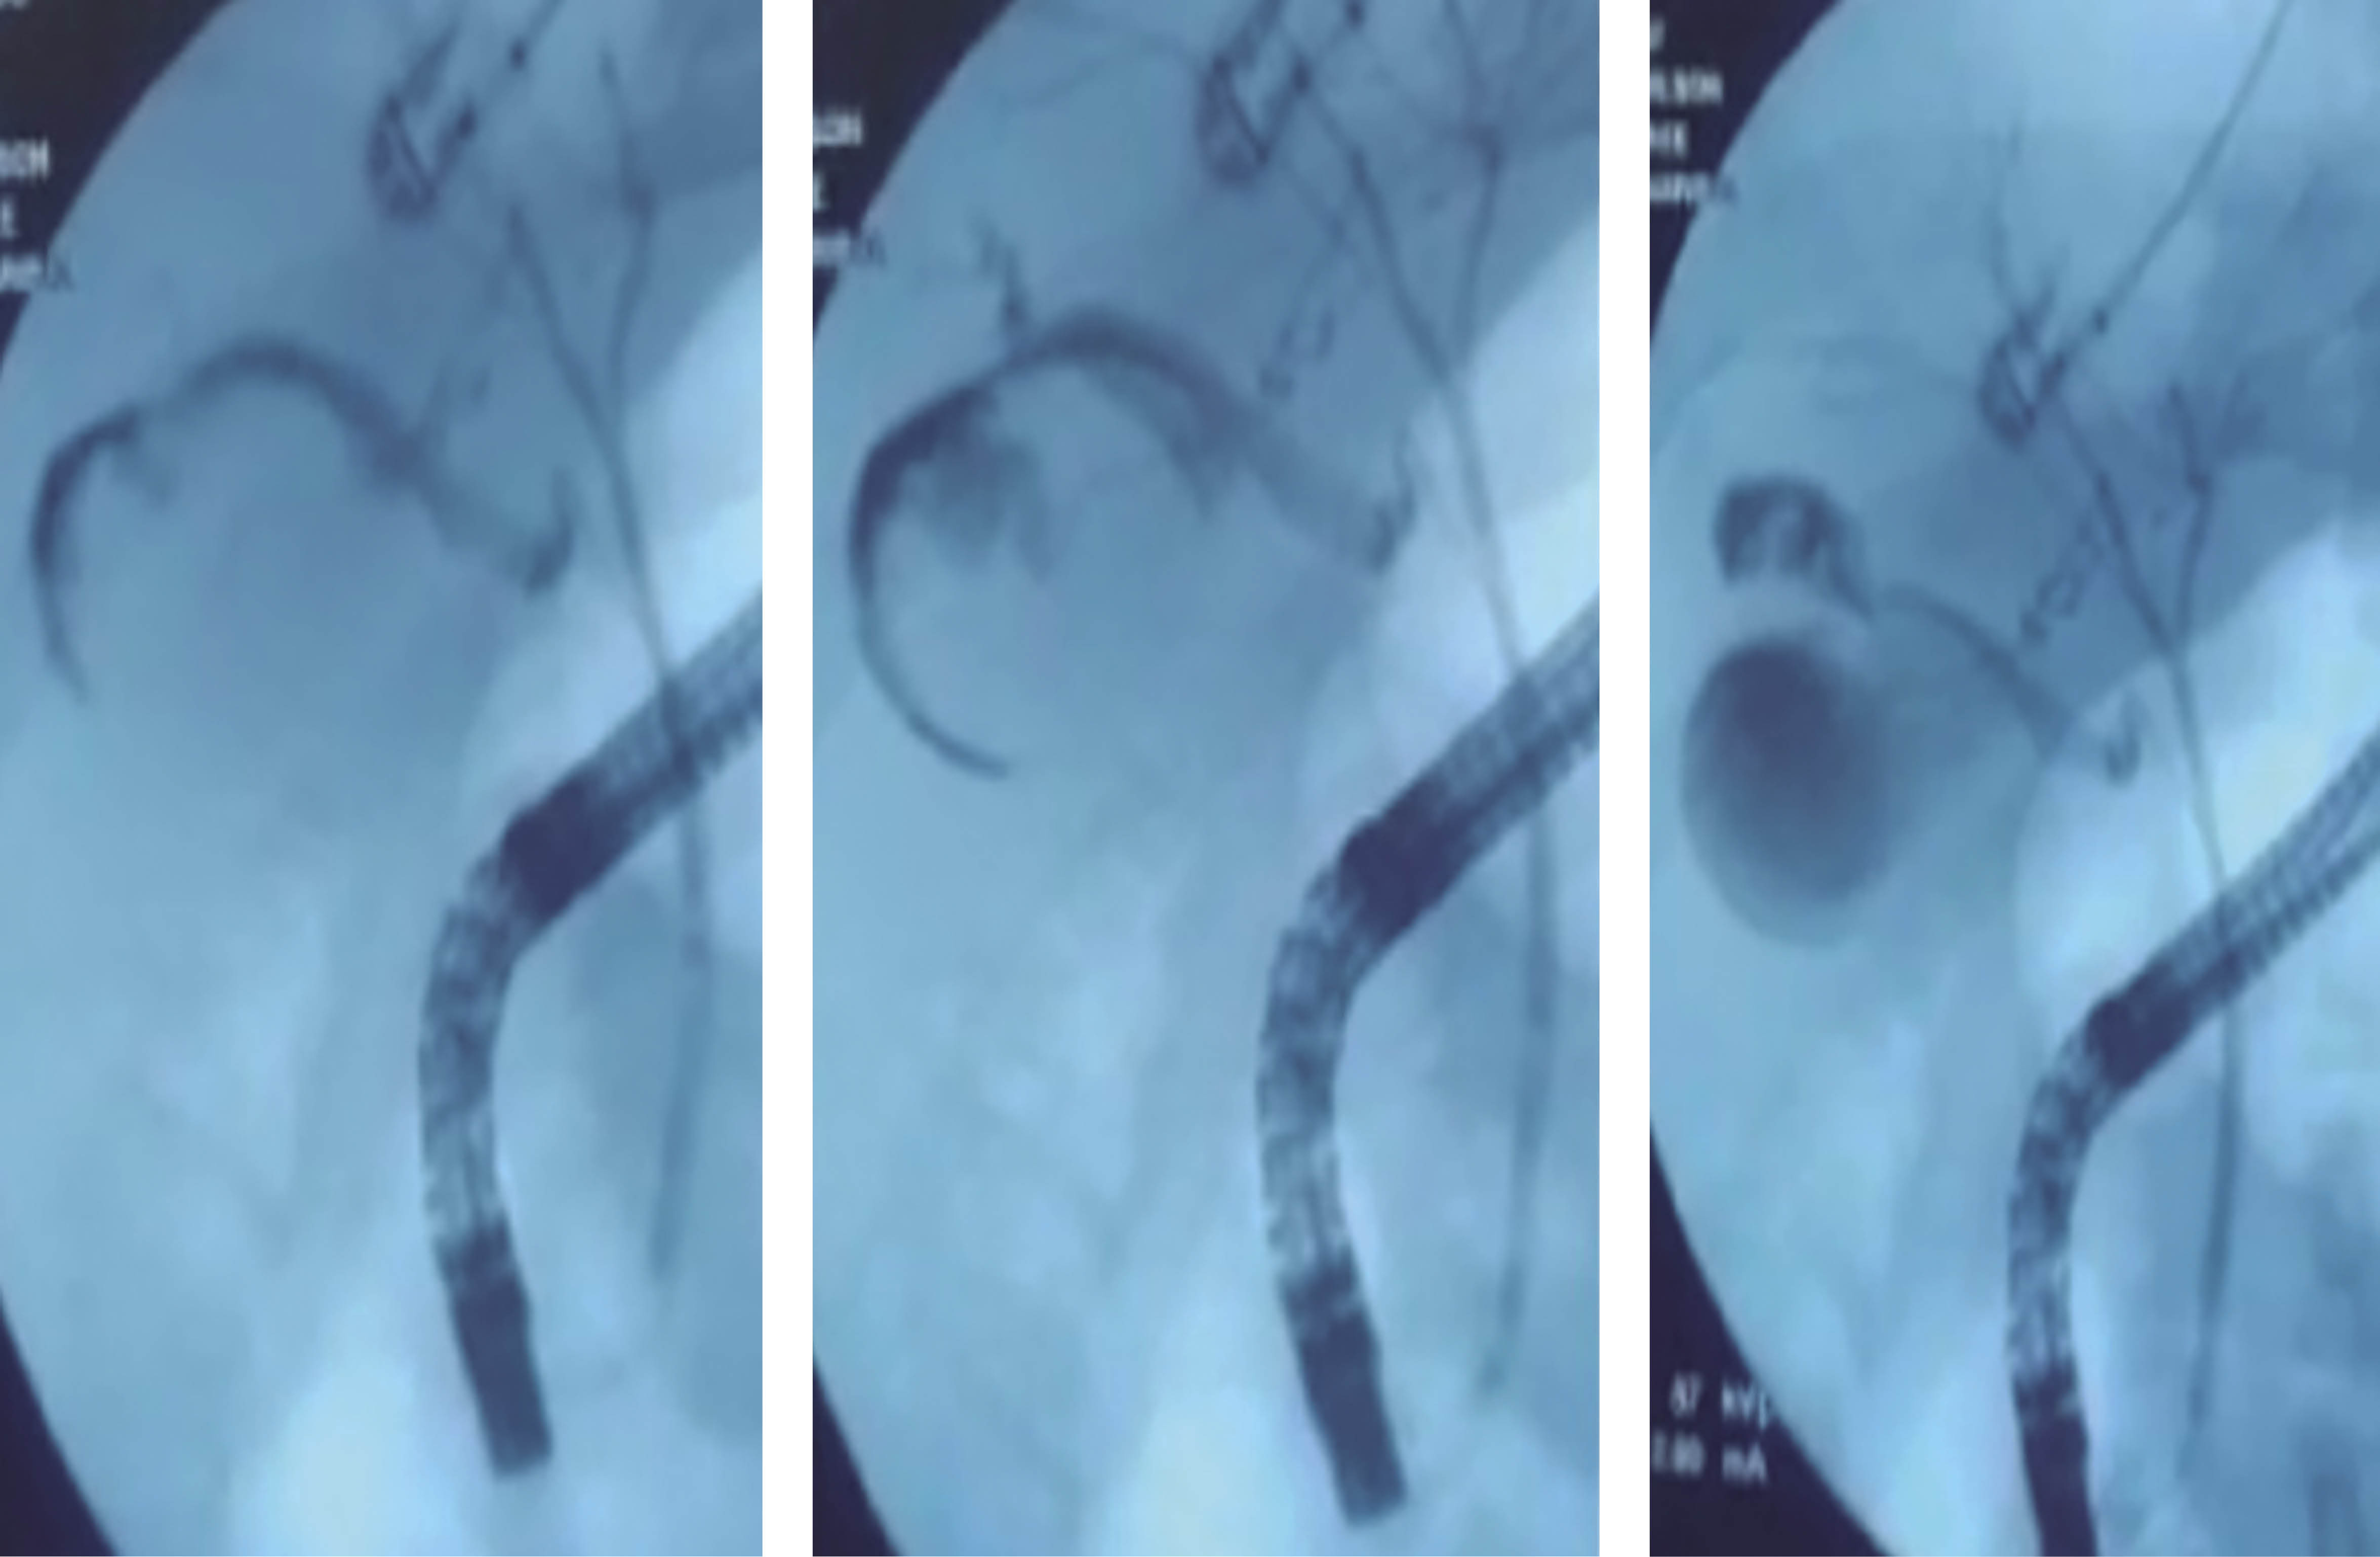

Following the study protocol, it was decided to start the oral route (four days and 15 hours later). An endoscopic retrograde cholangiopancreatography (ERCP) was performed that revealed a bile duct communicating to a small collection adjacent to the gallbladder (Figure 4). However, after a thorough review of the images, a disruption of the gallbladder wall adjacent to the hepatic parenchyma was observed, documenting the gallbladder lesion.

In penetrating abdominal trauma, the gallbladder injury usually appears in its free edge and conditions biliary peritonitis due to perforation of its wall.5 However, in the ERCP performed, it was observed that the lesion was on the side adjacent to the hepatic bed, classifying it as a perforation of the gallbladder, which is believed to be a protective factor for the development of symptoms of biliary peritonitis since the contrast leak observed in the ERCP was contained with the posterior wall of the gallbladder.

Nowadays, as a conservative therapeutic option, the ERCP with sphincterotomy and placement of an intra-biliary stent may be adequate.9 The European Society of Gastrointestinal Endoscopy (ESGE) has reported a success rate of up to 80-90% in management with ERCP plus stent insertion in case of partial bile duct injuries.10